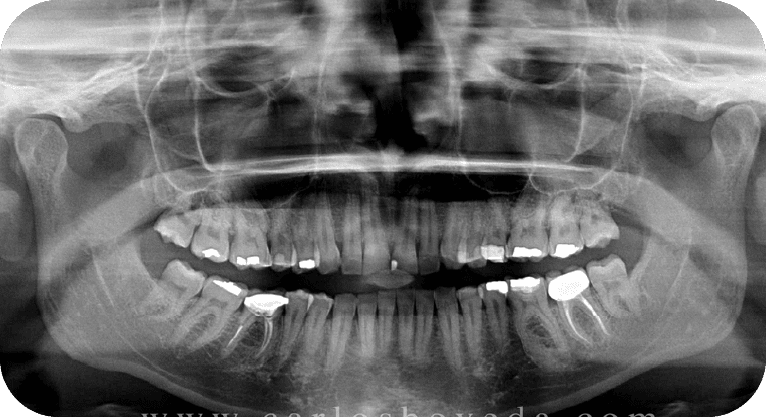

Male patient, “32” years old

Treatment: Root canal treatment

The patient required treatment on two teeth with irreversible pulpitis. Root canals were performed using a microscope, and the teeth were restored according to their damage, eliminating pain and avoiding extractions.